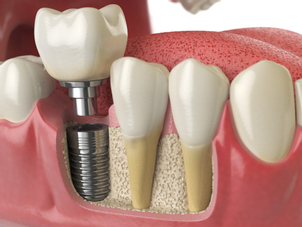

Le groupe Colgate nous indique que les implants dentaires, ou ancrages dentaires, sont des racines artificielles en métal, semblables aux vis, qui sont placées chirurgicalement dans l'os de la mâchoire, sous la gencive. Ils constituent une base solide pour fixer une ou plusieurs dents artificielles, appelées couronnes.

Les implants sont le moyen le plus fiable de remplacer les dents. Une fois les implants et les couronnes placées, le patient sera en mesure de mâcher de la nourriture comme s'il s'agissait de vraies dents. De plus, il est à l’heure actuelle quasiment impossible de détecter la présence d’un implant et d’une couronne tant qu’ils sont semblables esthétiquement et fonctionnellement aux dents naturelles.

La structure d'un implant dentaire